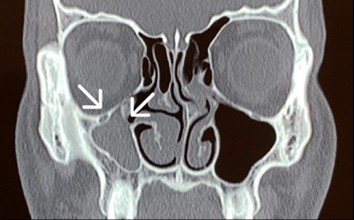

Enolftamia do olho direito

Exame de ressonância magnética com rebaixamento do assoalho da órbita direita